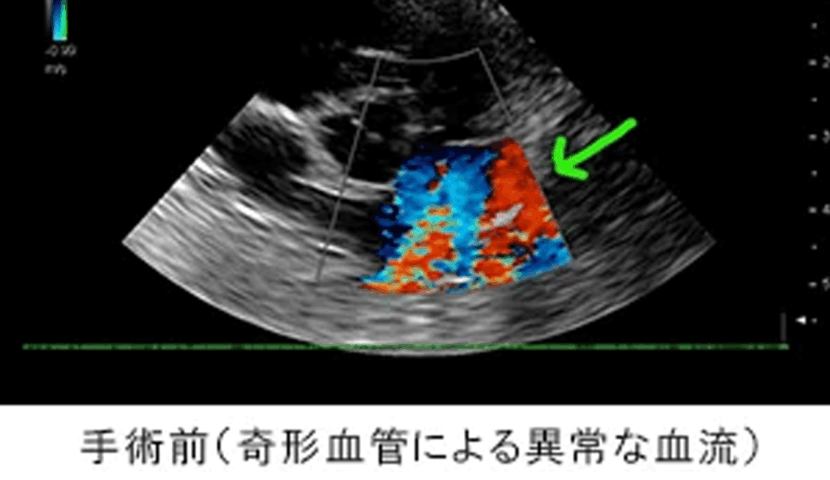

避妊手術の術前検査で心雑音を確認。超音波検査で心臓の血管に先天的な奇形を確認。

| 先天的な心臓奇形の中ではよく認められる疾患です。手術を早期に実施しなければ予後不良になることが多いですが、早期に治療を行えば、その後特別な治療の必要もなく、元気に過ごせます。 この症例は、術後から元気に日常生活を送っています。 |